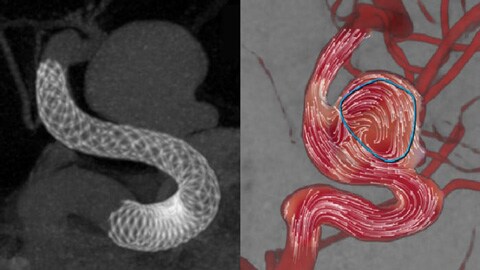

Mejorar la vista de los stents endovasculares, los desviadores de flujo y otros dispositivos, así como la morfología de los vasos hasta el nivel del perforador con SmartCT Vaso. Esta técnica de adquisición se basa en una exploración por TC de haz cónico y una inyección de contraste intrarterial. Se utiliza cada vez más para el seguimiento de aneurismas tratados con stents desviadores de flujo para comprobar la posición del dispositivo.

Calcular el flujo sanguíneo después del tratamiento

Flujo en el aneurisma después del tratamiento

AneurysmFlow evalúa los cambios en el flujo sanguíneo en el aneurisma; para ello calcula el cambio en la amplitud media del flujo del aneurisma (relación MAFA [Mean Aneurysm Flow Amplitude]) antes y después de la colocación del desviador de flujo.